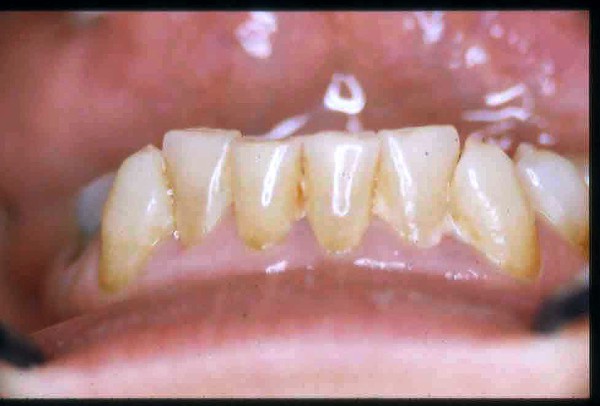

APRECIACIONES DIAGNÓSTICAS EN BASE A LA APERTURA MENTAL DEL CLÍNICO FRENTE A LO QUE EL PACIENTE PROPONE EN MUCHAS OCASIONES , LA DEMANDA DE LOS PACIENTES NOS INCLINAN A FOCALIZAR NUESTRA ATENCIÓN EN LAS PIEZAS DE LAS CUALES EL ENFERMO SE QUEJA. PACIENTE SEXO FEMENINO, 55 AÑOS, SE PRESENTA A LA CONSULTA DERIVADA POR COMPAÑERO GENERALISTA, QUIEN LLEVA MESES PROCEDIENDO A LA «DESINFECCIÓN» DE UN PRIMER PREMOLAR IZQUIERDO, EL QUE SE PRESENTA ABIERTO EN SU CONDUCTO EN EL AFÁN DE PERMITIR EL ESCAPE DE GASES DE UNA GANGRENA PULPAR. A LA INSPECCIÓN CLÍNICA SE OBSERVAN FACETAS PARAFUNCIONALES DE TERCER GRADO , ASINTOMÁTICAS, CON EVIDENTES DIFICULTADES MASTICATORIAS Y ESTÉTICAS , FALTA TOTAL DE SUS MOLARES INFERIORES, Y ADELANTAMIENTO PRONUNCIADO DE SU MANDIBULA, LA QUE CUESTA MANIPULAR DEBIDO A LA SITUACIÓN DE ESPASMO DE CASI TODA SU MUSCULATURA GNATICA. SE ESTUDIA EL CASO RADIOLOGICAMENTE, Y SE RELAJA EL SISTEMA MEDIANTE LAM. DE LONG REALIZANDO UN MONTAJE EN LA ORC OBTENIDA. NO SATISFECHOS CON EL RESULTADO, CONFECCIONAMOS UN JIG DE LUCIA, EL QUE DEJAMOS EN BOCA TODA UNA NOCHE, AL CABO DE LA CUAL REALIZAMOS UN NUEVO REGISTRO REALIZAMOS UN ENCERADO RÁPIDO DEL CASO, Y CONFECCIONAMOS UNA ESTRUCTURA OCLUSAL PLASTICA, QUE ADEMÁS REPONGA EL ASPECTO ESTÉTICO PERDIDO (FÉRULA DE RELAJACIÓN DE COMPONENTE ESTÉTICO), LO QUE PERMITE AL ENFERMO LUEGO DE DOS DÍAS DE USO, NO SOLO CORROBORAR LA COMODIDAD MASTICATORIA Y LA FALTA DE SÍNTOMAS MUSCULARES, SINO TAMBIÉN OBSERVAR APROXIMADAMENTE LA DIFERENCIA ENTRE LA SITUACIÓN INICIAL Y LO QUE PUEDE LOGRARSE MEDIANTE EL TRATAMIENTO. EL PACIENTE ADVIERTE LA MEJORÍA DE LA SITUACIÓN. ACEPTADO POR PARTE DEL MISMO EL TRATAMIENTO SUGERIDO, CREAMOS UN JUEGO COMPLETO DE PROVISORIOS EN BASE AL ENCERADO, Y PROCEDEMOS A TRATAR LA INFRAESTRUCTURA, QUE CONSISTE EN LAS ENDODONCIAS, SUS REFUERZOS A PERNOS DE ORO, LOS ASPECTOS PERIODONTALES DEL CASO, Y DOS IMPLANTES INFERIORES CON TÉCNICA SEMISUMERGIDA ,DE 5 MM DE ANCHO POR 12 DE LONGITUD, CON ANILLO DE ZIRCONIO , A LA ESPERA DE OSTEOINTEGRACIÓN, TRANSCURREN TRES MESES EN EL USO DE UNA NUEVA OCLUSIÓN CONSTITUIDA POR LOS PROVISIONALES, SEGÚN EL ENCERADO, QUE SE REALIZÓ SIGUIENDO LOS CÁNONES DE UNA OCLUSIÓN ORGÁNICA. COMPROBADA LA EFICACIA DE LA NUEVA SITUACIÓN, CON SUS DISCLUSIONES LATERALES Y POSTERO ANTERIORES CORRECTAS, CARECIENDO YA DE SINTOMATOLOGÍA MUSCULAR (SIN MIALGIAS, SIN MIOSITIS, Y CON UN GRADO DE APERTURA DE 4,50 CM), Y SIN SIGNOS EVIDENTES DE DESGASTE SOBRE EL MATERIAL DE LOS PROVISORIOS, ES DECIR: VERIFICANDO QUE EL PACIENTE YA NO BRUXA, VERTICALIZANDO EL CICLO MASTICATORIO /OTORGANDO ORC/ DIMENSIÓN VERTICAL /PROTEGIENDO A LAS PIEZAS `POSTERIORES DE IMPACTOS LATERALES RECIEN ENTONCES , MONTAMOS EN ARTICULADOR SEMI AJUSTABLE LOS MODELOS DE TRABAJO DEFINITIVOS. CONFECCIONAMOS ENTONCES LAS COFIAS INFRA PORCELANA, EN PORCELANA DE ALTA DENSIDAD EN EL SECTOR ANTERIOR Y EN ORO GALVÁNICO PARA EL SECTOR POSTERIOR PARA LUEGO COMPLETAR LA GUIA ANTERIOR , VERIFICANDO LA ALTURA DE LOS INFERIORES RESPECTO DEL LABIO INFERIOR Y CORROBORANDO LOS PUNTOS DE CONTACTOS INTER CANINOS, QUE CENTRALIZAN LA MANDIBULA Y VERTICALIZAN EL CICLO MASTICATORIO Y LAS DISCLUSIONES CANINAS QUE OTORGARÁN PROTECCIÓN A LOS SECTORES POSTERIORES. POSTERIORMENTE CHEQUEAMOS LA DISCLUSIÓN EN PROPULSIVA DE LA GUIA ANTERIOR YA TERMINADA. FIG38 FIG39 UNA VEZ OBTENIDO UN COMANDO ANTERIOR EFECTIVO, COMO LO ES LA GUIA ANTERIOR CON TODOS SUS COMPONENTES, PROCEDEMOS A REALIZAR LAS TABLAS PREMOLAR / MOLAR DE AMBOS LADOS Y OBSERVAMOS QUE LOS PUNTOS INTEROCLUSALES DE CONTACTO SEAN SUFICIENTES Y CUMPLAN SU OBJETIVO DE OTORGAR ESTABILIDAD MESIO DISTAL Y VESTÍBULO LINGUAL. TRANSCURRIDO UN AÑO DE FINALIZADO EL TRATAMIENTO, REALIZAMOS UN CHEQUEO POST OPERATORIO DEL CASO, EN TODOS LOS PARÁMETROS ANTERIORMENTE MENCIONADOS, Y OBSERVAMOS LA ABSOLUTA ESTABILIDAD DEL MISMO EN TODOS SUS NIVELES Y TEJIDOS.